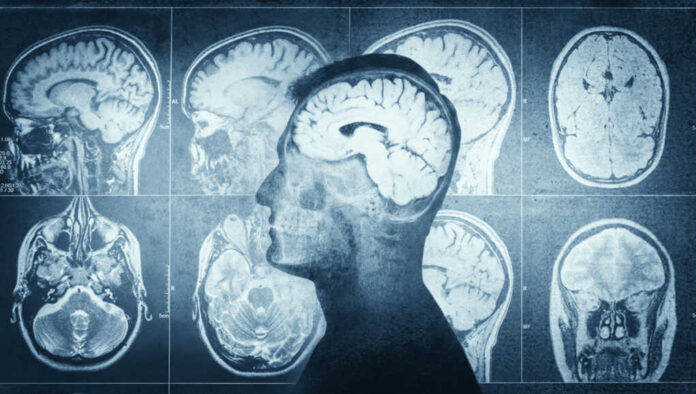

Researchers at AdventHealth Research Institute published results in the Journal of Sport and Health Science on January 22, 2026, demonstrating that 130 healthy adults ages 26 to 58 achieved measurable brain rejuvenation through a simple exercise program. Participants who completed 150 minutes of moderate-to-vigorous aerobic activity weekly—matching American College of Sports Medicine guidelines—saw their brain-predicted age difference drop by approximately 0.6 years over 12 months. Control group members experienced a slight brain age increase during the same period, creating nearly a one-year gap favoring exercisers. This marks the first randomized trial quantifying brain age reversal in younger cohorts using MRI technology.

Brain-predicted age difference measures how old a brain appears on MRI scans compared to chronological age, with higher values linked to poorer cognitive performance and dementia risk. The trial’s 0.6-year reduction may seem modest, but researchers note these changes compound over decades when maintained consistently. Dr. Erickson highlighted that midlife intervention provides a “head start” versus late-stage fixes. The brain age improvements occurred independently of fitness levels, brain-derived neurotrophic factor, or body composition changes, suggesting direct neuroprotective mechanisms that scientists are still working to understand fully.